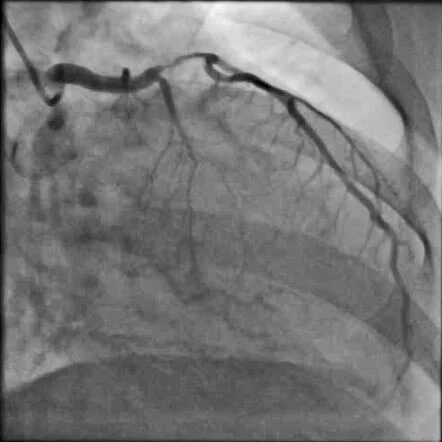

Angiogram shows severe LAD stenosis with thrombosed plaque

Post-stenting: Absolutely gorgeous result!